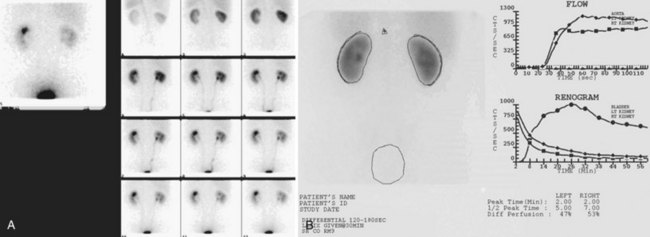

Figure 4–34 A, Transverse view of the bladder in this female patient demonstrates the uterus (U). B, Sagittal view of the bladder shows the uterus posterior to the bladder.

Figure 4–35 In this transverse view of the bladder, urine “jets” emerging from the left (arrow) and right (arrowhead) ureteral orifices are demonstrated by power Doppler.

Bladder volume can be calculated manually by obtaining measurements in the midtransverse and midsagittal planes (Fig. 4–36). Numerous studies have shown that for bladder volumes between 100 and 500 mL, such calculated volumes are within 10% to 20% of the actual bladder volume (Roehrborn et al, 1986).

Figure 4–36 Measurement of bladder volume using this formula: bladder volume = width (transverse plane) × height (transverse plane) × length (midsagittal plane) × 0.625. In the sagittal plane, the dome (D) of the bladder is to the left and the prostate (P) to the right.